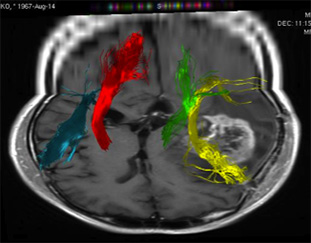

3.トラクトグラフィー Tractography

脳内の神経線維を詳細に調べ、脳腫瘍と重要な神経線維がどのような関係にあるのかを調べ、手術の時にこれらが損傷しないような手術プランを計画します。

(左図)ピンク色が脳腫瘍、緑色は運動の神経線維を示しています。

(右図)赤色は右の運動神経線維、緑は左の運動神経線維。黄色は言語機能の連絡をする神経線維を示しています。